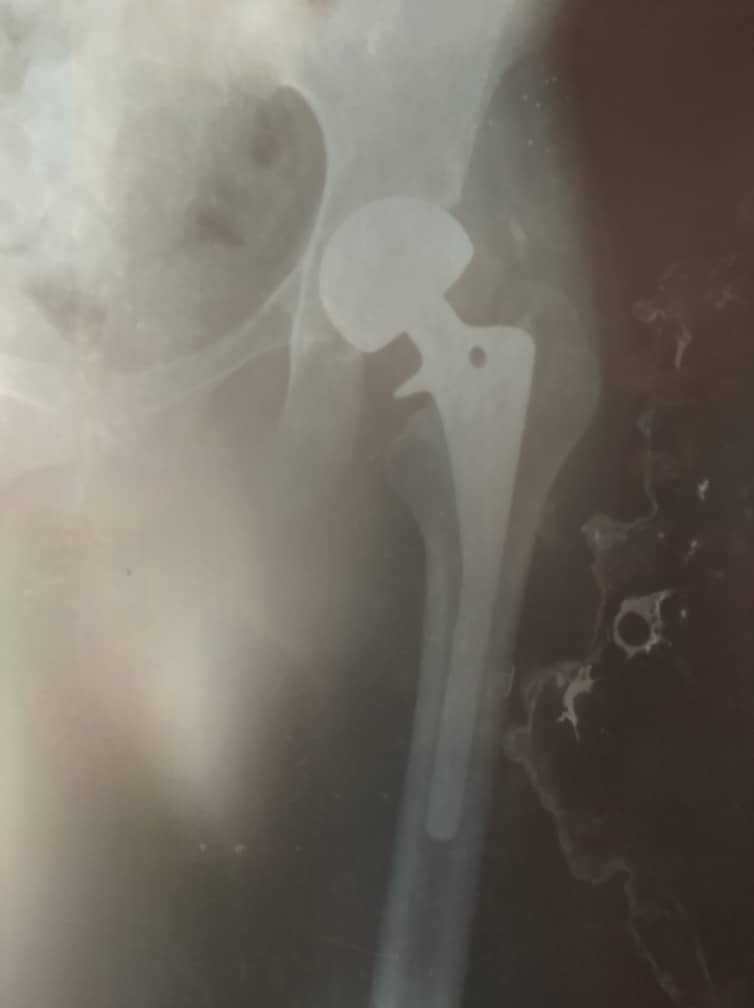

Para ese entonces, me operaron y colocaron una prótesis incorrecta en la cadera, que con el paso del tiempo se ha vencido y me está provocando severas lesiones en el área, lo cuál me causa dolores de fuerte intensidad y me impide caminar.

Los médicos me han diagnosticado signos de protusión acetabular lo cual amerita nueva intervencion quirúrgica, para el recambio de endoprótesis de cadera izquierda cementada, que deben realizarme lo más pronto posible, debido a que con el paso de los días los huesos se siguen dañando y hasta corro el riezgo de sufrir daños irreparables.